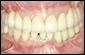

最近のインプラント治療は、以前のように、噛めることを優先とした治療だけでなく、見た目(審美性)まで考慮した治療へと移行してきています。また、以前までは、骨がない部分にはインプラント治療はあきらめざるを得なかったところに、骨を再生させ、骨量を増大させることによりインプラントを植立することが可能になってきています。しかし、このような治療には術者の高度な技術が要求されるのも確かです。

また、インプラント治療を受けられる患者さんでは、その他の歯牙や歯周組織においても問題を抱えている場合が多く、一口腔単位での治療が必要になる場合がほとんどであるといえます。噛み合わせや歯の根っこの治療(根間治療)、歯周治療、虫歯の治療をおろそかにしてインプラント治療の成功は望めないといっても過言ではないでしょう。 |